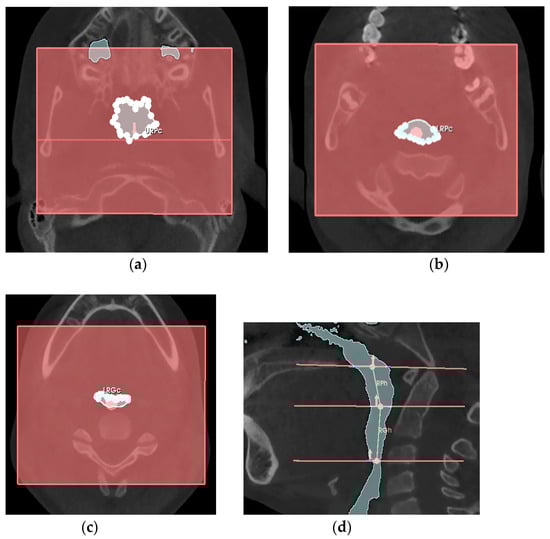

- the retro-palatal volume section was modeled as a right truncated cone, F, with an upper circumference URPc (from which the diameter URPd = URPc/π was derived), a lower circumference LRPc (from which the diameter LRPd = LRPc/π was derived), and a height RPh;

- the retro-glossal volume section was modeled as a right truncated cone, G, with an upper circumference LRPc (from which the diameter LRPd = LRPc/π was derived), a lower circumference LRGc (from which the diameter LRGd = LRGc/π was derived), and a height RGh.

| URPc (mm) | Upper circumference of the retro-palatal volume, measured on the axial slice where the Ba-PNS plane superiorly defines the retro-palatal volume. |

| LRPc (mm) | Lower circumference of the retro-palatal volume, measured on the axial slice where the horizontal plane of the soft palate inferiorly defines the retro-palatal volume and superiorly defines the retro-glossal volume. |

| LRGc (mm) | Lower circumference of the retro-glossal volume, measured on the axial slice where the horizontal plane of the epiglottis inferiorly defines the retro-glossal volume. |

| RPh (mm) | Height of the retro-palatal volume, the distance measured on the median sagittal slice of the retro-palatal volume from the midpoint of the upper limit defined by the Ba-PNS plane to the midpoint of the lower limit defined by the horizontal plane of the soft palate. |

| RGh (mm) | Height of the retro-glossal volume, the distance measured on the median sagittal slice of the retro-glossal volume from the midpoint of the upper limit defined by the horizontal plane of the soft palate to the midpoint of the lower limit defined by the horizontal plane of the epiglottis. |